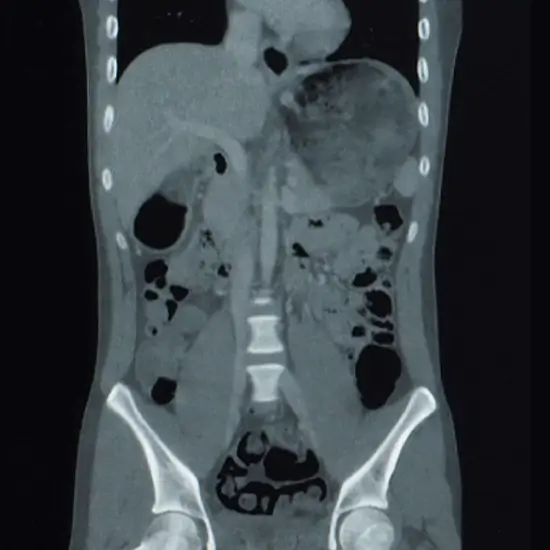

CECT Lower Chest and Upper Abdomen is Contrast Enhanced Computed Tomography of the lower chest and upper abdomen. It is an imaging procedure that uses contrast media, an x-ray beam, and a computer to obtain images of the lower chest and upper abdomen. For this procedure, contrast media is given to the patient for clear images of organs. This scan is used to identify various lung-related disorders, detect/diagnose the presence of lung cancer, abdomen pain, location of kidney stones, cancers, appendicitis, Crohn's disease, etc.

Doctors recommend CECT Lower Chest and Upper Abdomen to detect the underlying problems in the lower chest and upper abdomen.

• * Detect/diagnose the presence of lung cancer and abdominal pain. Abnormalities in the chest, Location of kidney stone, appendicitis, Crohn's disease, etc.